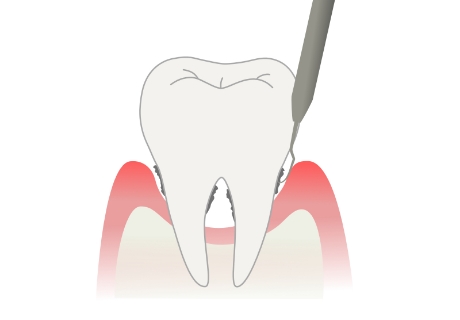

スケーリング

毎日の歯みがきでは落としきれないプラークや歯石を除去します。

ルートプレーニング

スケーリングでは落としきれない歯周ポケットの奥のプラークや歯石を除去してから歯根を滑らかに仕上げます。